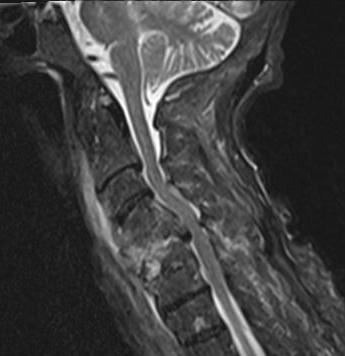

MRI

Investigation of choice

- 95% accurate

- diagnose vertebral osteomyelitis

- look for epidural abscess

Early

- T1 loss of distinction between disc and end plate

- T2 loss of normal disc intranuclear cleft

- specific for infection

Gadolinium T1

- ring enhancement

DDx

Tumour

- preservation of disc

TB

- no increased T2 in disc